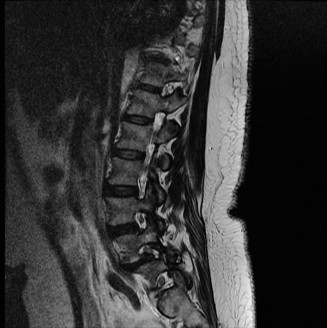

fractures of the anterior or posterior elements. The hallmark feature is a translation deformity that can be noted by misalignment of the vertebral bodies in the coronal and/or sagittal planes. A lumbar spine MRI is obtained, images from which are shown inFigures 1–34 and 1–35. Based on the information presented, the type of neurological injury is best characterized as which of the following? 1. Cauda equina injury

Figure 1–34

Figure 1–35

Discussion

The correct answer is (A). The MRI demonstrates the L2 fracture with canal compromise. In this patient, the conus medullaris of the spinal cord terminates at the T12–L1 level. The fracture is at the L2 level. Thus, the neurological injury is at the level of the cauda equina, distal to the conus medullaris and spinal cord. The patient’s neurological examination is consistent with this type of injury with the presence of lower extremity weakness, intact rectal tone, and perineal numbness, though this can vary.